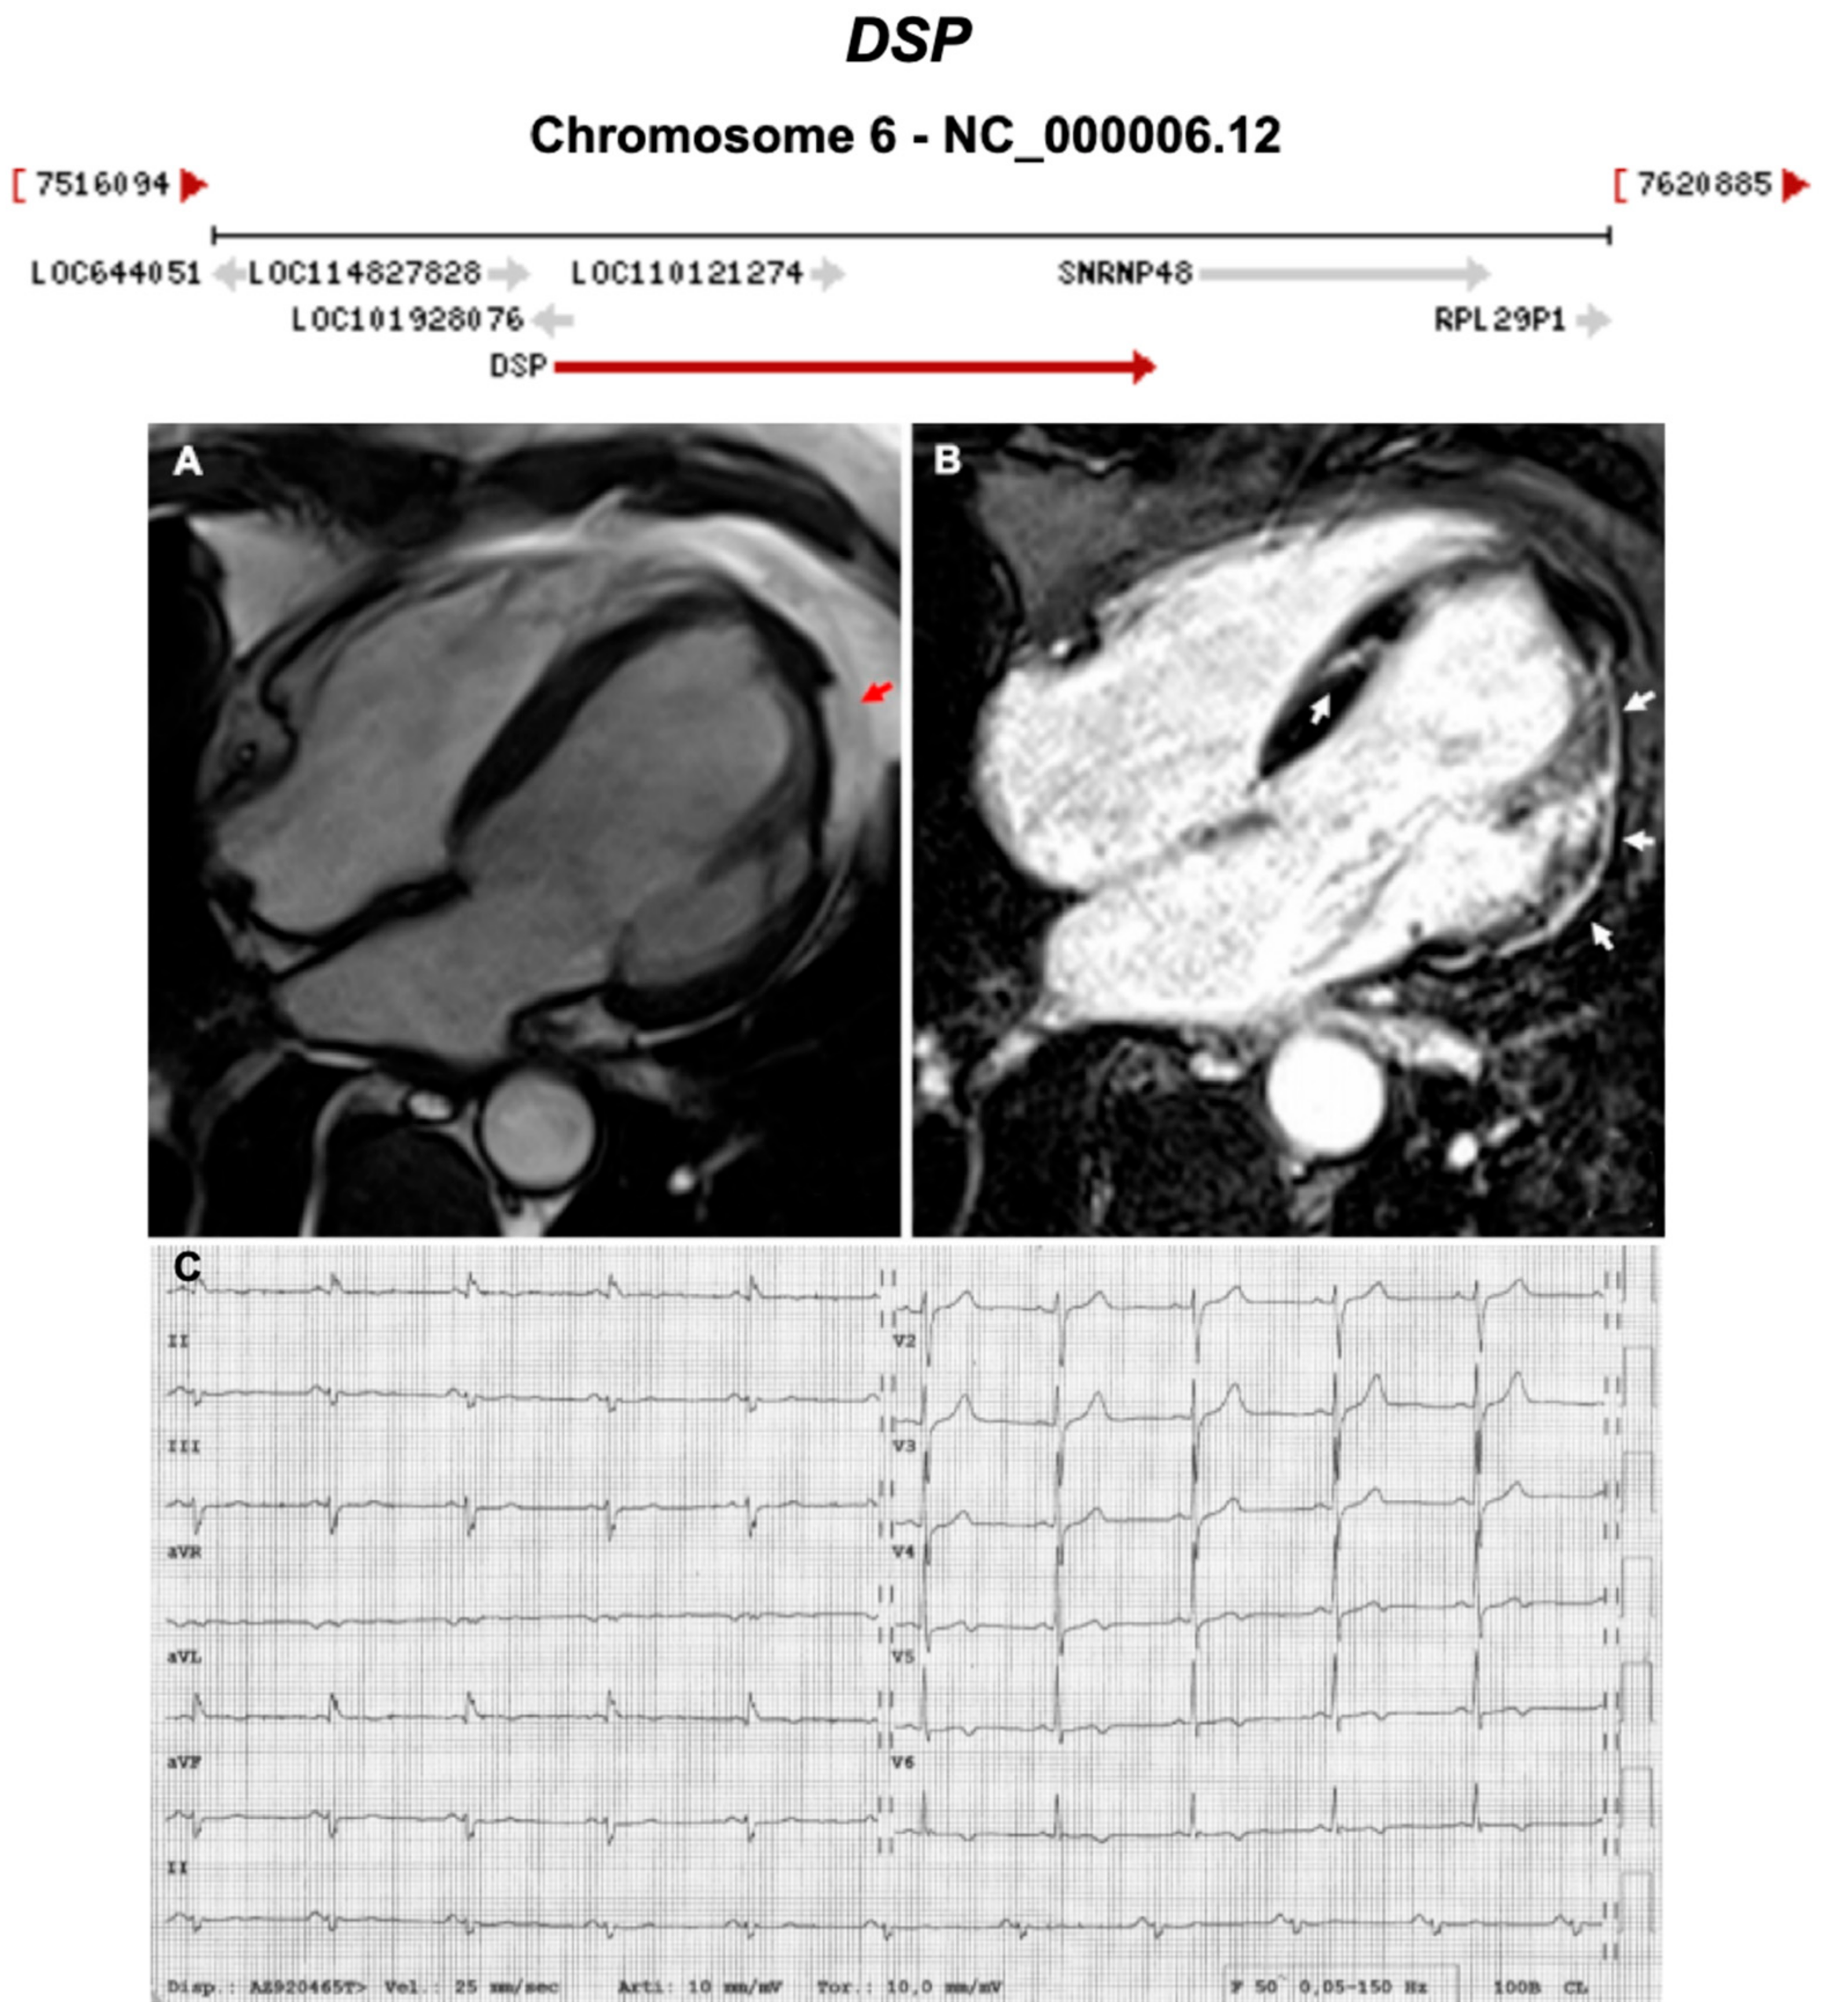

| DSP | Desmosome | 1–13% | AD | LV, BIV | ARVC8 | 6p24.3; 24 | Cardiocutaneous Syndrome AR (Carvajal), can also have cardiocutaneous with AD | Definitive for ARVC |